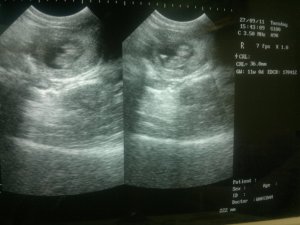

Week 11

Photos : Pergerakan baby yang berpusing-pusing ketika proses ultrasound (scan)

Videos – Kelihatan baby sedang berpusing-pusing dan bergerak-gerak. Pada awalnya tidak bergerak sangat, tetapi setelah beberapa saat kemudian baby bergerak-gerak seolah-olah tahu kehadiran ibubapanya yang sedang melihatnya.hehe